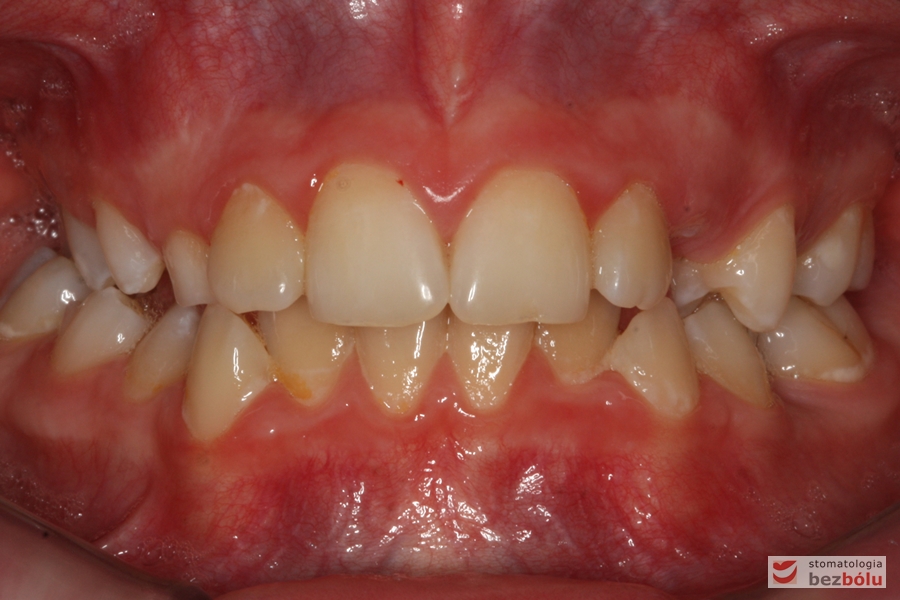

Rodzice zgłosili się z pacjentem celem rutynowej kontroli ortodontycznej. Wykonano OPG i po analizie modeli diagnostycznych stwierdzono brak miejsca dla wyrzynania dolnej prawej piątki stałej oraz zwężenie szczęki wraz z rotacją górnych zębów szóstych. W łuku górnym w pierwszym etapie leczenia zastosowano Rotator, celem odrotowania 6-tek stałych oraz ekspansji łuku w wymiarze poprzecznym. Następnie zamontowano aparat stały metalowy do uszeregowania zębów w łuku. W łuku dolnym miejsce odtwarzano stosując aparat stały i odpowiednią mechanikę leczenia. Leczenie aktywne trwało 3,5 roku, po czym zastosowano terapię retencyjną (retainer stały w żuchwie oraz Płytkę Hawley’a w szczęce).